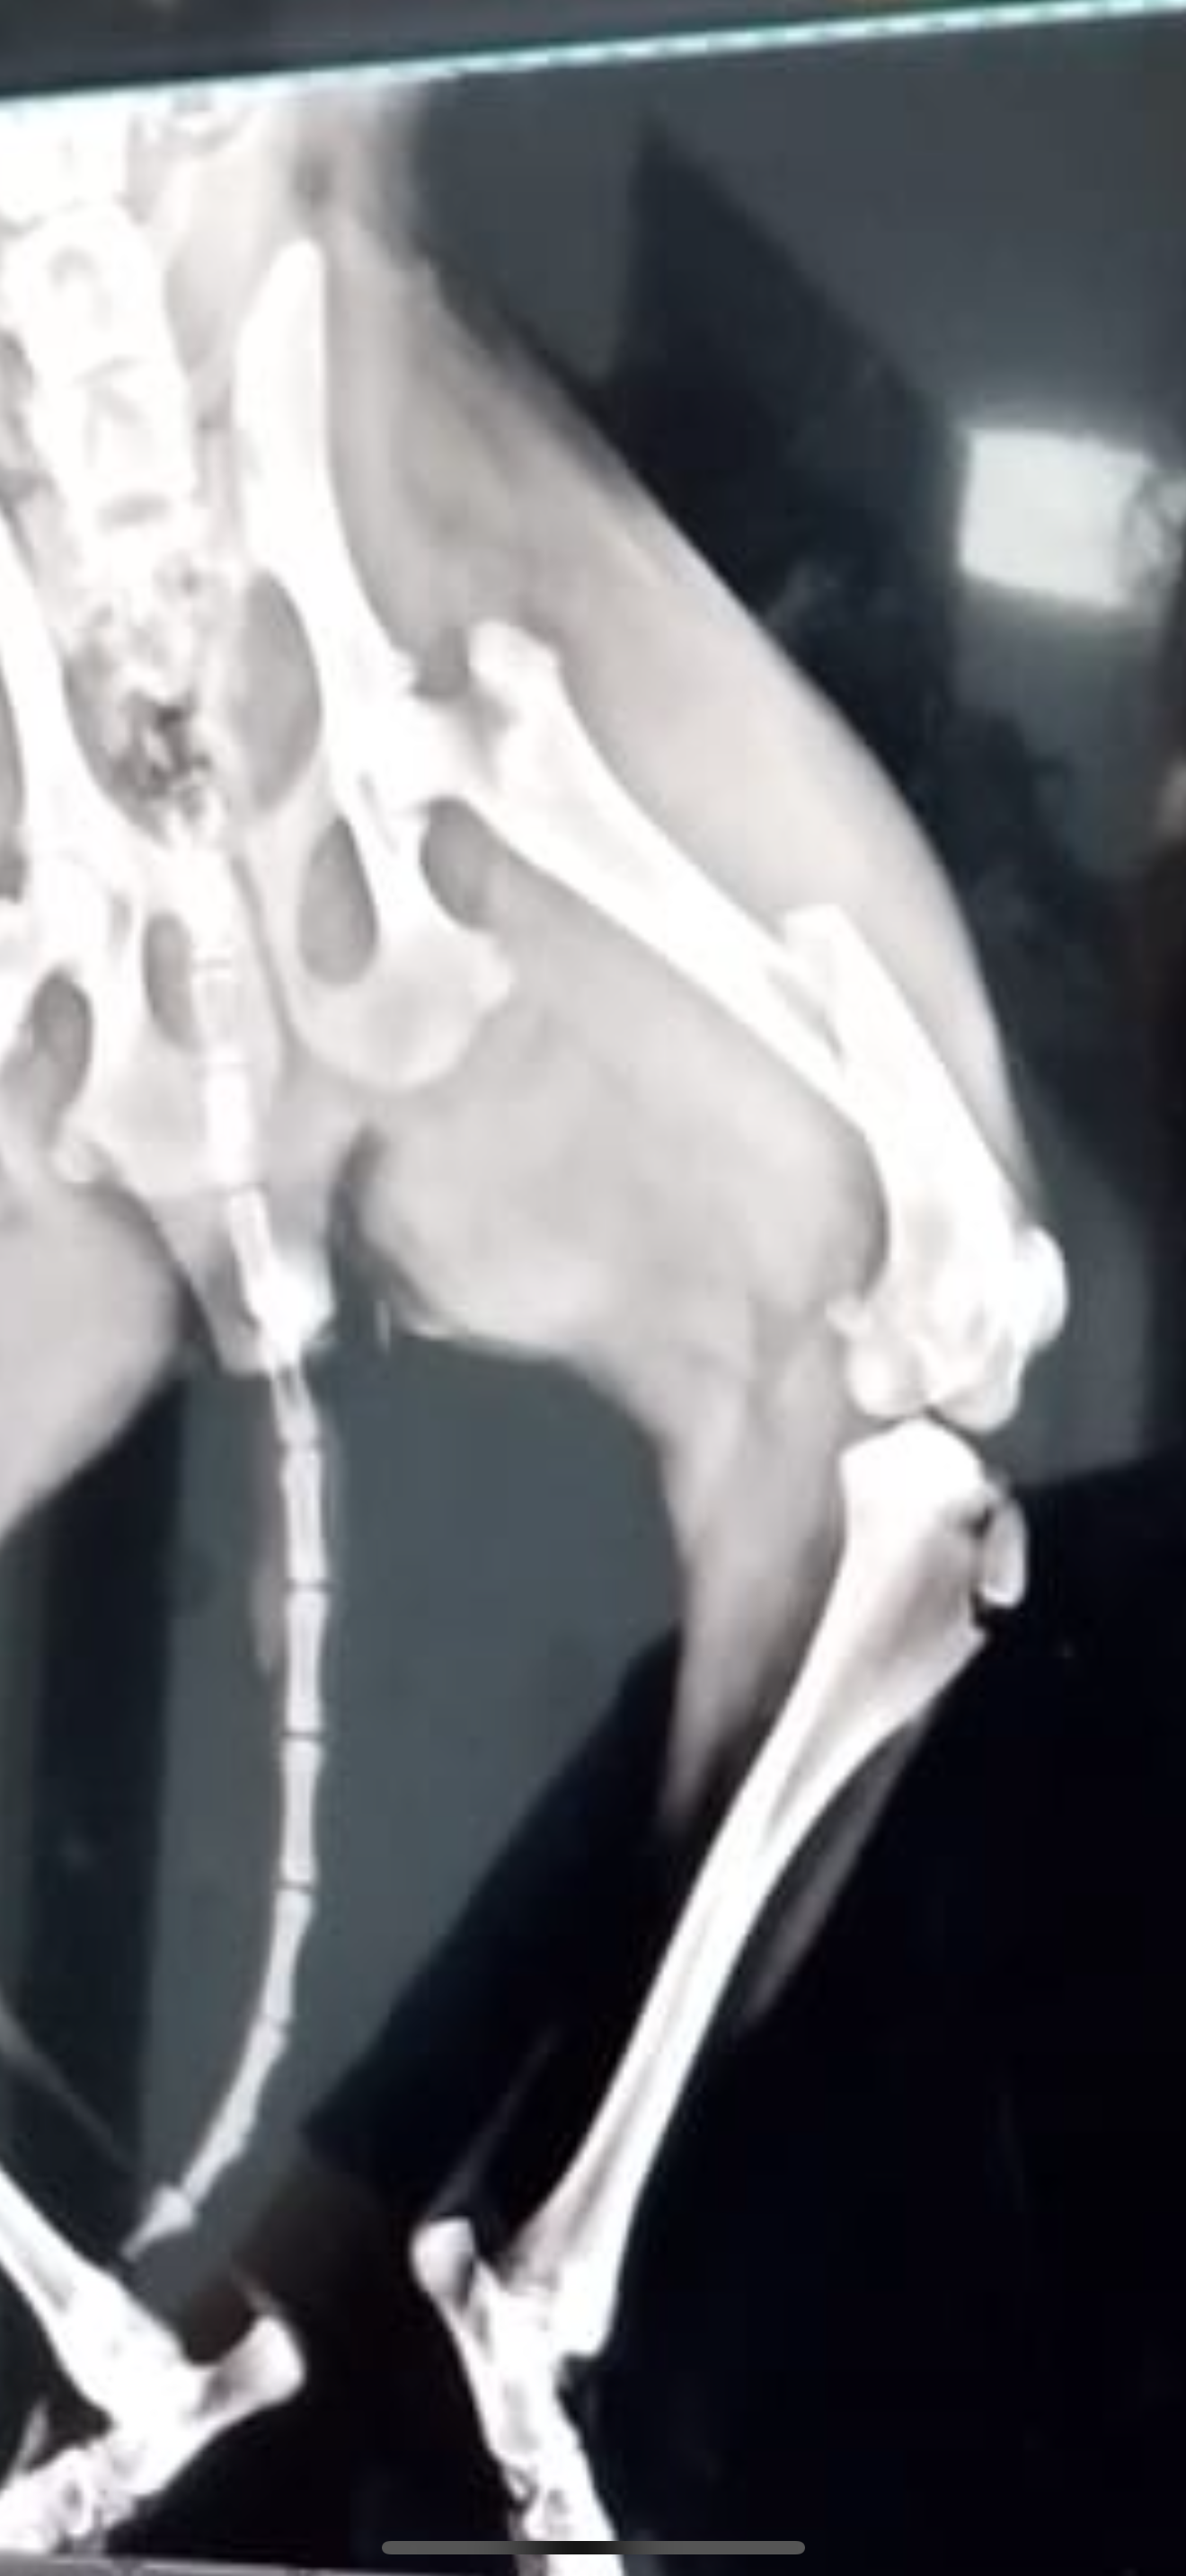

Our newest addition to our home is this dog, named Chikona, who followed us for three days on the streets and won our hearts. We also rescued her brother, too. Unfortunately, she was just run over by a car that was delivering food supplies to our finca and compound fractured her femur. She is going into surgery as I write this.

Just updated*** the vet just told us that her intestines are in her thorax and it’s a much more serious situation.